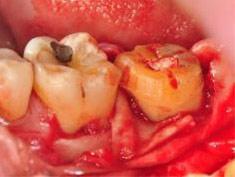

B圖為牙齦溝內切線合併牙齦下切線與垂直鬆弛性切線。

C圖為牙齦溝內切線合併牙齦下切線與垂直鬆弛性切線。

D圖為牙齦翻瓣清創後之頰側觀,#37其近心側有一寬且深,深達9毫米,型態為三壁之骨內缺損(three walls intrabony defect),頰側之根叉並無侵犯。

E圖為牙齦翻瓣清創後之舌側觀,其近心側繞舌側有一寬且深,深達5毫米,型態為合併雙壁、三壁之骨內缺損(combined two-three walls intrabony defect),舌側之根叉侵犯為1毫米。